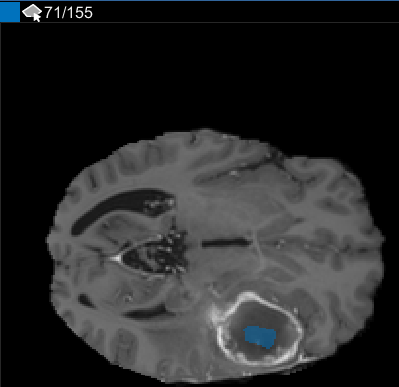

Можно также просмотреть каждый срез объема на панели « Срезе». Для перехода от среза к срезу используйте ползунок в нижней части панели. Вы можете увидеть опухоль на срезе 35 через срез 88. По умолчанию на панели « Срезе» отображается том, ориентированный вдоль оси X-Y, но изменить его можно с помощью кнопок в разделе Ориентация (Orientation) панели инструментов на вкладке Сегмент (Segmenter). Панель « Срез» также находится там, где для определения маски используются инструменты рисования.

После использования интерполяции проверьте отдельные срезы, чтобы увидеть, создала ли интерполяция удовлетворительные ROI. Обратите внимание, что информация только для чтения на срезе 71 не заполняет весь объект, который вы хотите сегментировать. Настроить информацию только для чтения можно вручную с помощью инструмента «Кисти краски». Также можно использовать один из инструментов на вкладке Automate. Например, можно использовать Active Contours, чтобы вырастить ROI на срезах, где он не заполняет полный размер опухоли. Можно также использовать Алгоритм Добавления, чтобы задать свой собственный алгоритм для работы с ROIs.